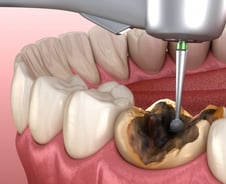

치아·잇몸·혀 등 구강의 건강 상태가 '전신'의 건강을 좌우할 수 있다는 연구 결과가 속속 나온다. 그간 구강 중에서도 치주염, 치아 상실에 한해 전신 건강과의 연관성이 연구됐지만, 최근엔 생존율과 암 발생률에 구강 건강이 관여한다는 새로운 연결고리가 발표돼 주목된다. 먼저, 구강질환이 암 발생률을 높인다는 사실이 국내 연구 결과로 입증됐다. 서울대병원 공공진료센터 김계형 교수와 서울시보라매병원 공공부문 이승연 박사는 2009년 구강검진을 받은 성인 384만5280명을 대상으로, 2006~2019년 국민건강보험공단 진료 기록과 통계청 사망 자료를 연계해 10년 이상 추적 관찰했다. 연구팀은 구강질환을 △충치 △치은염 △치아 상실의 세 가지로 구분해, 유무에 따라 전체 암과 부위별 암의 발생률·사망률을 분석했다. 그랬더니 전체 암 발생은 총 18만1754건으로, 구강질환이 있는 사람에서 그렇지 않은 사람보다 암이 더 많이 발생했다. 특히 치아 상실이 있는 경우 대장암은 13%, 간암은